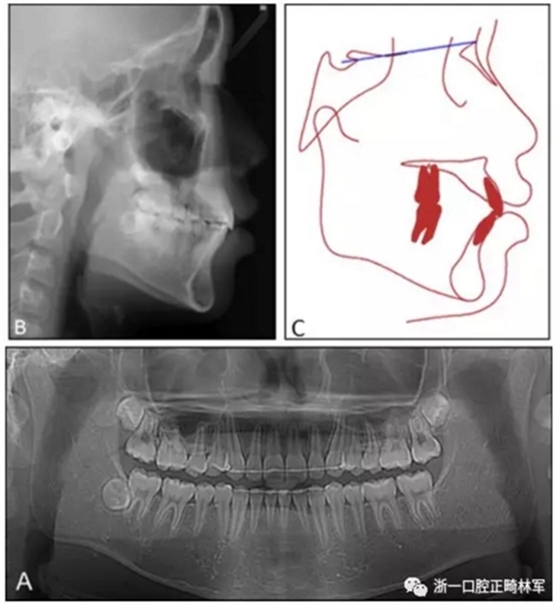

患者面型得到較大改善,治療后開唇露齒解決,側(cè)貌突度減小?;颊叩母埠细采w恢復(fù)正常,磨牙關(guān)系與尖牙關(guān)系維持I類。

治療后全景片上示牙根平行度可,無明顯牙根吸收。側(cè)位片示,上頜切牙直立(U1-FH,從121°變?yōu)?07°),鼻唇角增加,從86°變?yōu)?01.5°。在重疊圖中可見,上頜切牙與磨牙分別后移了2.5mm與3mm,下頜平面角減小了1°,合平面角增加了2°。

10個月后復(fù)查,療效穩(wěn)定,無明顯復(fù)發(fā)。